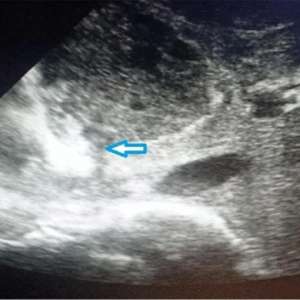

Инфекционная аневризма сосуда головного мозга

Мужчина, 70 лет

Родом из Новой Зеландии, направлен с проявлениями дисфазии и нехарактерного поведения.

Сопутствующие заболевания отрицает, ранее курил трубку, в настоящее время живет в отдаленной местности в доме на колесах.

В течение нескольких последних месяцев пациент неоднократно обращался к своему терапевту с жалобами на постоянную тошноту, усталость и потерю веса. Он был госпитализирован в терапевтическое отделение с диагнозом «кахексия» в связи с непреднамеренной потерей веса примерно на 20 кг за 2 месяца.

Лечащий врач, наблюдавший его во время первой госпитализации, отметил, что у него был слегка повышен уровень С-реактивного белка. Была выполнена КТ ОГК, ОБП и ОМТ, но признаков злокачественных новообразований или эмболии не было выявлено. Также выполнены ЭГДС и колоноскопия - отклонений не выявлено. Обращал на себя внимание новый комбинированный систолический и низкочастотный ранний диастолический шум над аортой. Пациент был выписан и рекомендовано проведение ЭХО-КГ в амбулаторных условиях.

В ожидании результатов амбулаторного обследования пациент пришёл в гости к своей сестре в состоянии спутанности сознания и с затруднённой речью. Сестра пациента вызвала скорую помощь.